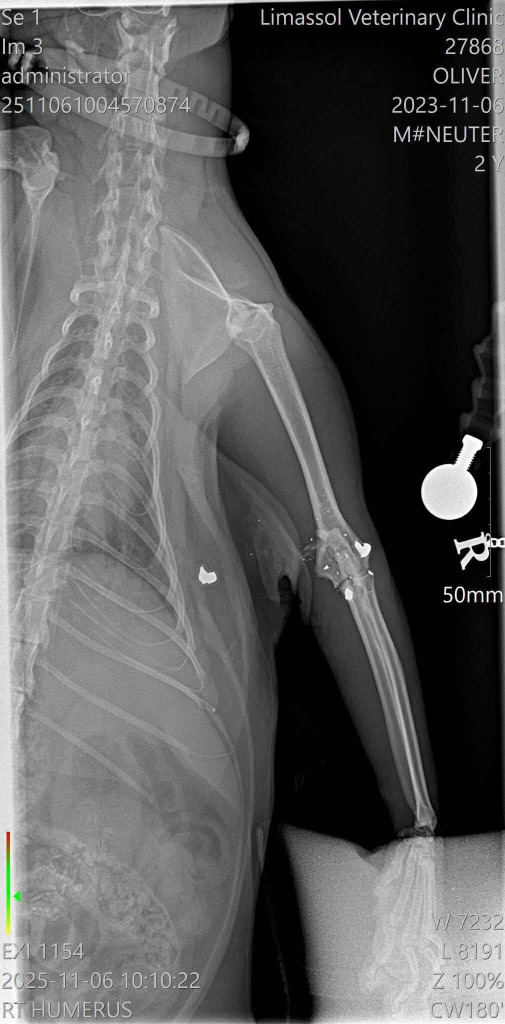

Oliver

Recovering from surgery and needs a special friend.